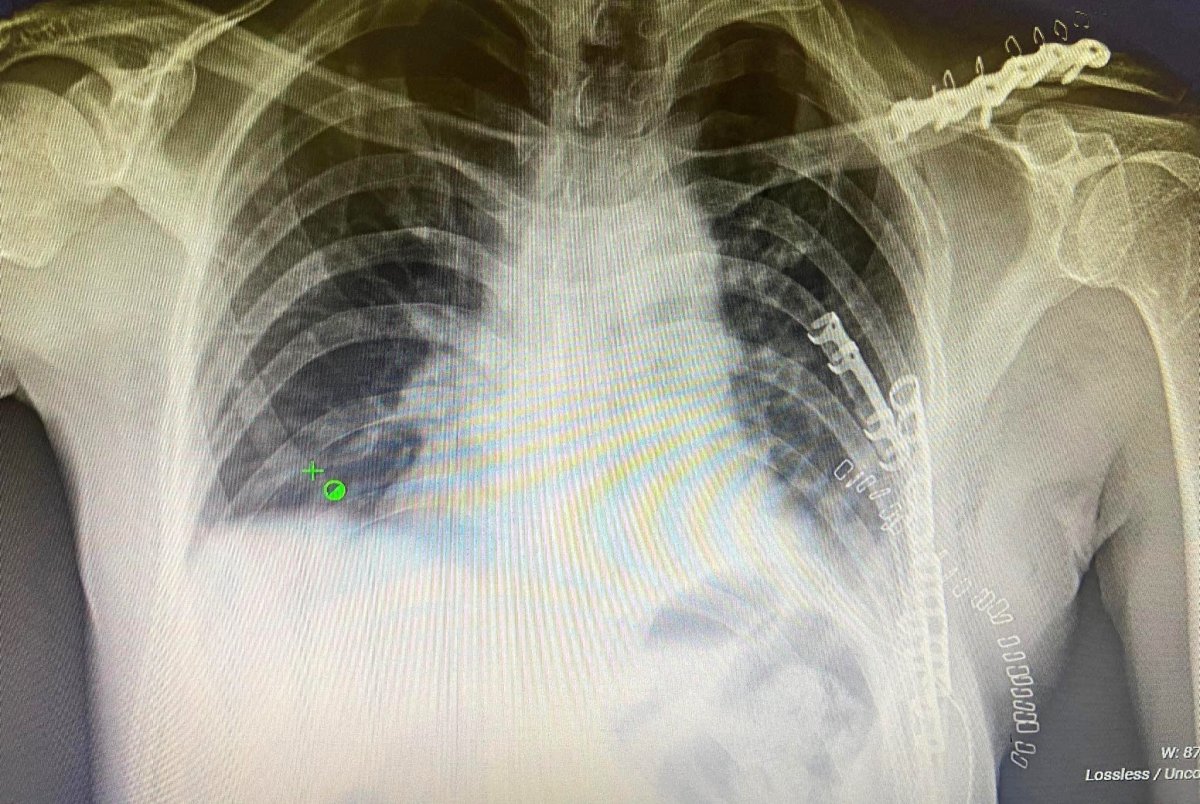

Гэмтэл согог судлалын үндэсний төвийн Хавсарсан гэмтлийн мэс заслын тасгийн эмч, мэргэжилтнүүд цээжний хөндийн битүү гэмтэл болон дурангийн мэс засал, олон хавирганы тогтворгүй хугарлыг бэхлэх эмчилгээг эх орондоо нутагшуулан, эмнэлгийн тусламж үйлчилгээнд өдгөө 7 дахь жилдээ хэрэгжүүлэн ажиллаж байна.

Уг ажлын үр дүнд Сүхбаатар, Өмнөговь, Дорноговь, Хэнтий, Говь-Алтай, Булган аймгийн эмнэлэгт цээжний хөндийн битүү гэмтэл болон дурангийн мэс засал, хавирганы хугарлыг бэхлэх эмчилгээ хийж эхэлснээр орон нутгийн иргэдэд цаг алдалгүй тусламж үйлчилгээ үзүүлж, лавлагаа шатлалын эрүүл мэндийн байгууллагын ачаалал, төвлөрлийг сааруулахад чухал ач холбогдолтой ажил болсон билээ.